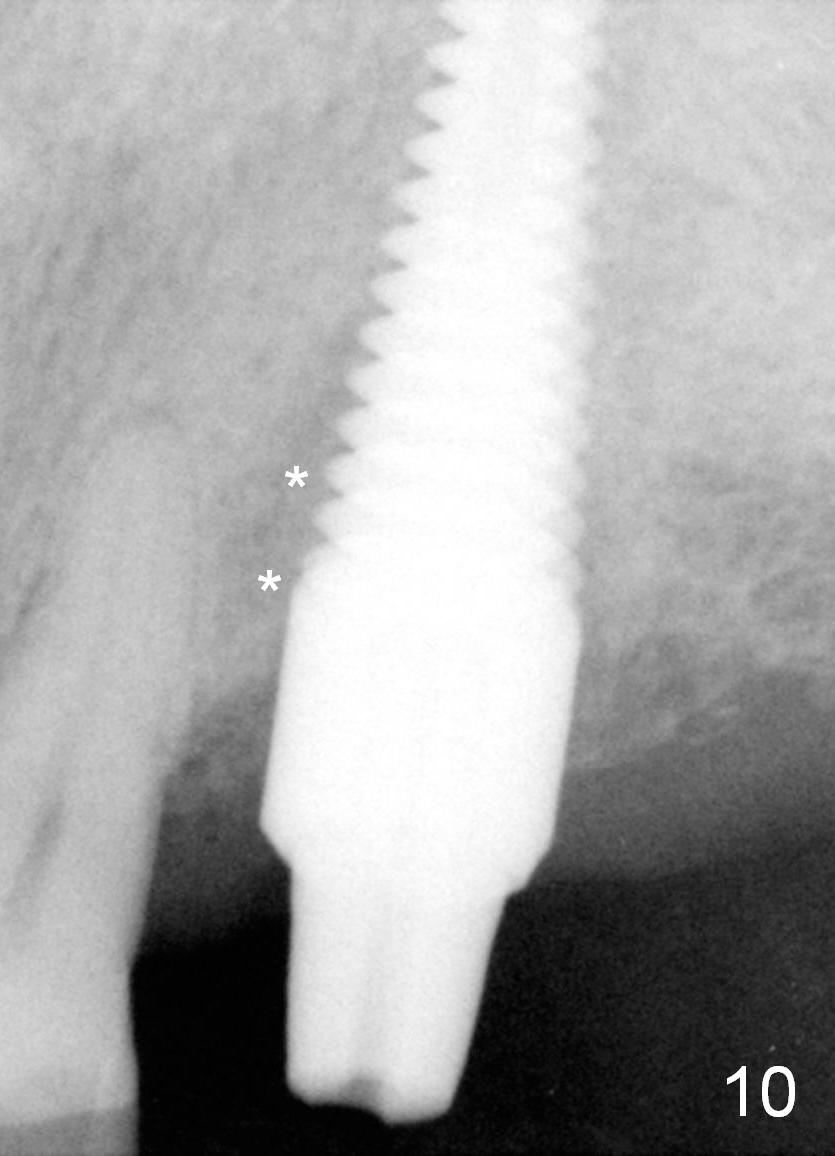

There appears bone growth in the mesial gap 3 months postop (Fig.10 *). There is no bone loss 2.5 years post cementation (Fig.11).